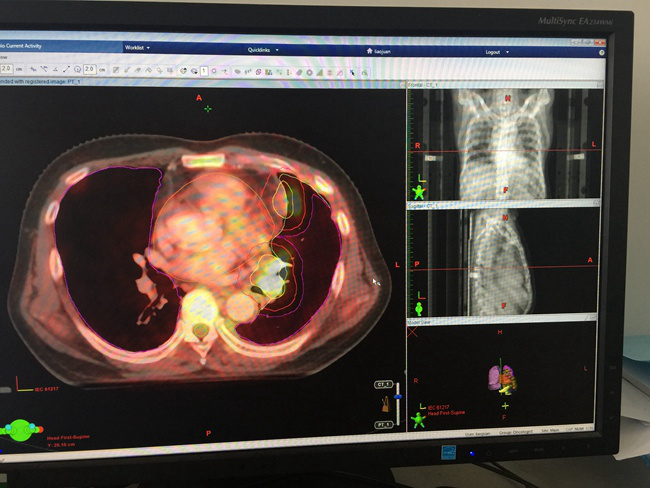

靶区勾画是放射治疗过程中的关键一步。目前主要依靠CT扫描采集的图像进行病灶区域的勾画,但CT对于软组织的分辨率相对较低,确定病灶范围准确性有限,MRI则对异常软组织的检测分辨能力更加敏感,通常可以发现CT不能发现的病变。PET-CT在CT影像的基础上加上了分子功能影像,能够更精准、清晰的捕捉到病变组织。该院常务副院长杨怡萍表示:“图像融合技术将三种不同特征的影像在同一平台显示、对比与分析,可以显著提高肿瘤病变诊断的准确性及放疗靶区勾画的精准性,治疗中可以提高肿瘤区域照射剂量,降低正常组织照射剂量,因此降低了区域复发率,避免了不必要的放射损伤,提高患者远期生存。例如肺癌的放疗中,通过融合PET-CT后制定的放疗计划可以降低约8%的局部复发率。同时配合性能先进的TrueBeam加速器让放射治疗真正做到精准、高效,给患者带来更好的疗效,更少的副作用。“ 在杨怡萍常务副院长的带领下,陕肿放疗素股

拥有国际最先进的也是西北地区唯一的美国Varian公司高剂量率容积旋转调强(TrueBeam)直线加速器,它可以对全身各部位肿瘤实施影像引导下(IGRT)的三维适形调强放疗(IMRT),并融合素股3.0MRI及PET/CT影像,实现多模式影像配准进行准确的生物靶区勾画,在治疗时进行3D容积成像,使用精密治疗床实现误差修正,可以精确地解决靶区的位置和形状的不确定性,在确保肿瘤得到充分照射的前提下,更好地保护正常组织。